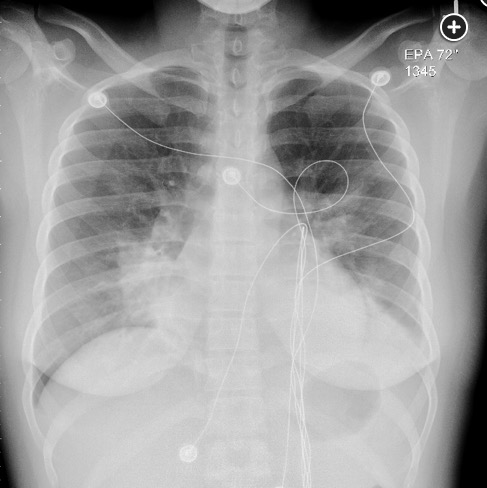

A 28-year-old woman with no known medical conditions presents to the ED with a 3-day history of fever, productive cough, and increasing shortness of breath. Prior to the onset of this illness she had experienced no other symptoms or signs, and there is no relevant epidemiological history related to her illness. On exam, she is acutely ill but is oriented to time, place, and person. Her temperature is 39.2°C, with a BP of 96/78 mm Hg, pulse of 122/min, and respirations of 34/min. Chest exam reveals diffuse crackles with consolidation findings over left lung base posteriorly. The remainder of her exam is unrevealing. Room air blood gases are a pH of 7.56, PCO2 of 29 mm Hg, and PO2 of 54 mm Hg. Her chest radiographs are shown in Figure 1 and Figure 2. Blood cultures drawn at the time of presentation are positive in 12 h for Streptococcus pneumoniae. Tests for HIV and influenza are negative. Based on this clinical presentation, what is the most likely finding that would explain the underlying basis for this patient’s clinical presentation of bacteremic pneumococcal pneumonia?

The underlying conditions for severe pneumococcal infection parallel the indications for pneumococcal vaccine: functional or anatomical asplenia, HIV infection, lymphoma (both Hodgkin and non-Hodgkin), and multiple myeloma. An additional risk factor for severe pneumococcal infection is alcohol use disorder. Analogous to herpes zoster infection (in which immunosuppression is a classic risk factor for the development of multidermatomal zoster), compromise of humoral immunity (as can occur with multiple myeloma and lymphoma) predisposes to the development of multilobar pneumococcal pneumonia. Given this patient’s severe clinical course with multilobar involvement, a search for an immunocompromising state would be prudent. Her age argues against multiple myeloma but in favor of lymphoma, which could result in a defect in her humoral immunity. The finding of intrathoracic lymphadenopathy, which was suspected based on the findings on her admission chest radiographs, would be consistent with such a diagnosis (choice A is correct).